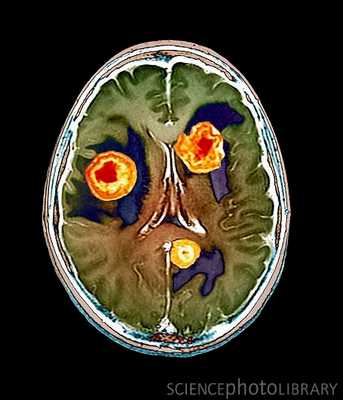

Компьютерная томография при опухолях мозга

Злокачественные новообразования сопровождаются многочисленными нарушениями. Нативное КТ опухоль головного мозга показывает на основе прямых и косвенных признаков. После выявления патологического очага проводится контрастное усиление для верификации метастазов, определения размеров очага. Усиление необходимо для оценки перифокальной паренхимы.

Прямые маркеры опухоли головного мозга:

- Понижение или повышение плотности мозгового вещества;

- Участки обызвествления внутри аномального очага;

- Разнородные зоны аномальной плотности.

Описанные маркеры свидетельствуют о наличии аномального очага. При небольших размерах образования диагностика основывается на косвенные проявления:

- Локальный отек мозга вокруг новообразования;

- Атипичное расположение сосудистого сплетения, срединных структур;

- Гидроцефалия;

- Закупорка путей движения спинномозговой жидкости;

- Расширение желудочков.

Выраженность косвенных признаков имеет разную степень. Морфология, расположение, степень отечности зависит от преобладания цереброваскулярного или дисциркуляторного компонента, ишемических, атрофических расстройств. Отложение солей кальция внутри участка повышенного, пониженного сигнала свидетельствует о длительном существовании образования. Описанные критерии характерны для сосудистых опухолей. Внутри новообразования плотность снижена, а вокруг - увеличена.

Показывает КТ опухоль головного мозга после контрастирования лучше. Увеличение гетерогенности после усиление - признак злокачественности. Зона характеризуется множественными участками сниженной и повышенной плотности, фрагментами некроза ткани.

После инъекции контраста КТ мозга при доброкачественных очагах не визуализирует гетерогенность. Низкая интенсивность доброкачественной опухоли после усиления сохраняется. Квалифицированный врач лучевой диагностики по результатам томографии может предварительно предложить вид опухоли головного мозга:

- Очаги сниженной плотности с четкими очертаниями характерны для астроцитомы;

- Глиомы зрительного нерва имеют повышенную плотность, которая усиливается после контрастирования;

- Менингиомы - округлые четки зоны средней плотности. Зона ограничивается от здоровой паренхимы, имеет участки известковых отложений;

- Сигнал от метастазов редко отличается от здоровой паренхимы без контрастирования. После усиления можно верифицировать от коры.

После введения контрастного вещества метастатические очаги четко отграничиваются. Периферическая часть отграничивается от паренхимы четким кольцом за счет отека, некроза, центральной кистой.